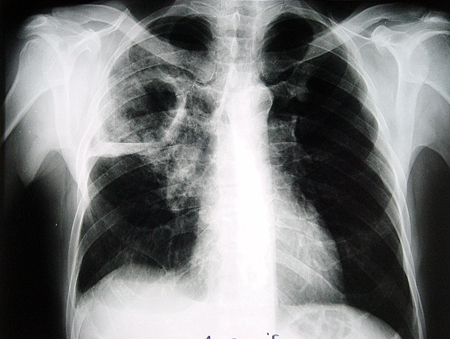

Chest x-ray: cavity is usually located in the upper lobes. [Figure caption and citation for the preceding image starts]: Chest x-ray showing an abscess-like cavitating lesion due to tuberculosisFrom the collection of Dr Ioannis P. Kioumis [Citation ends].